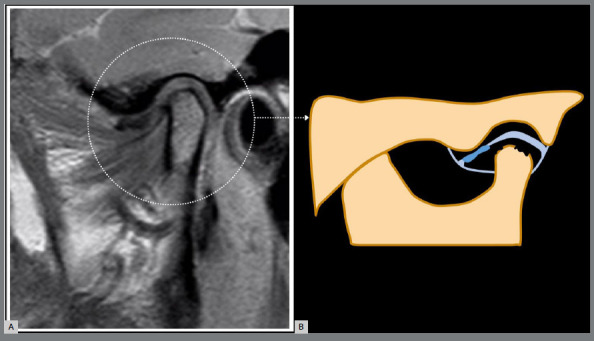

导言:骨关节炎(OA)是一种渐进性退行性疾病,以软骨逐渐退化、软骨下骨重塑、滑膜炎和慢性疼痛为特征。这种疾病会影响各种大小关节,包括颞下颌关节(TMJ)。然而,由于临床和影像学上的异质性,治疗 OA,尤其是阻止或减少疾病进展具有挑战性。越来越多的学者认为,这种异质性涉及不同的表型或亚群,可通过疾病的病理生理学和结构表现的差异来辨别。即使在颞下颌关节内,这些表型也可能显示出不同的临床特征、实验室参数、生化标志物和成像标准。最近的研究提出将核磁共振成像作为颞下颌关节 OA 的参考标准,强调其与组织病理学变化高度一致。基于核磁共振成像的表型为了解疾病进展和治疗反应提供了一条很有前景的途径,有可能为预后和治疗计划提供有价值的见解:本文介绍了ROAMES-TMJ(颞下颌关节骨性关节炎MRI快速合格评分),用于评估颞下颌关节OA临床试验的结构合格性。

Introduction: Osteoarthritis (OA) is a progressive degenerative disease characterized by the gradual degradation of cartilage, remodeling of subchondral bone, synovitis, and chronic pain. This condition impacts various large and small joints, including the temporomandibular joint (TMJ). However, addressing OA, particularly in impeding or reducing disease progression, is challenging due to its clinical and imaging heterogeneity. Authors are increasingly suggesting that this heterogeneity involves different phenotypes or subpopulations, discernible by variations in the disease's pathophysiology and structural manifestations. Even within the TMJ, these phenotypes may display distinct clinical features, laboratory parameters, biochemical markers, and imaging criteria. Recent research has proposed MRI as a reference standard for TMJ OA, highlighting its substantial agreement with histopathological changes. MRI-based phenotypes offer a promising avenue for understanding disease progression and treatment response, potentially providing valuable insights for prognosis and treatment planning.

Objective: This article introduces the ROAMES-TMJ (Rapid OsteoArthritis MRI Eligibility Score for TMJ) to assess the structural eligibility of individuals for inclusion in TMJ OA clinical trials.